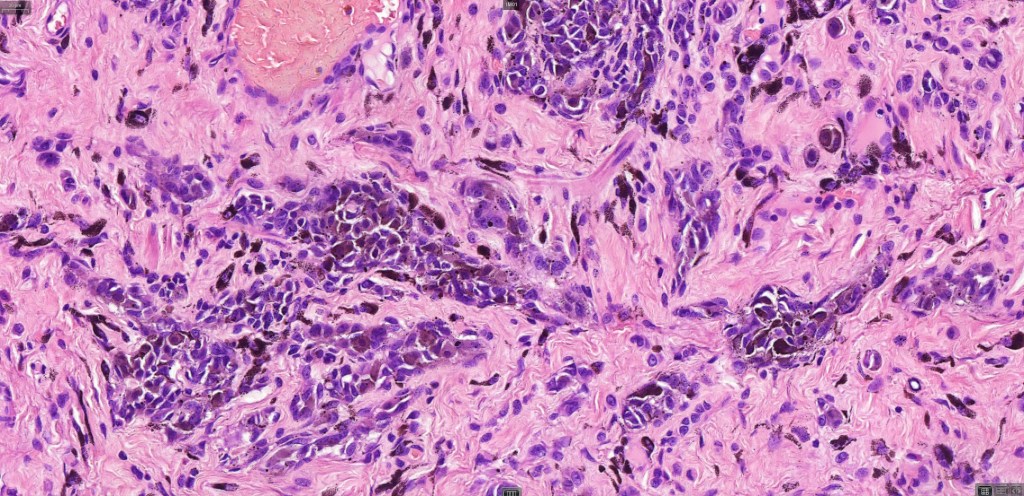

This is uncommon and presents clinically with a history of recent change in color of a common or less often congenital nevus causing concern for melanoma by the clinician. Some, but not all are probably deep penetrating and combined nevus variants. Others may represent follicular type-A cell nests. It is characterized by the presence of deep nest(s) of type -A nevus cells surrounded by & with overlying type-B nevus cells.